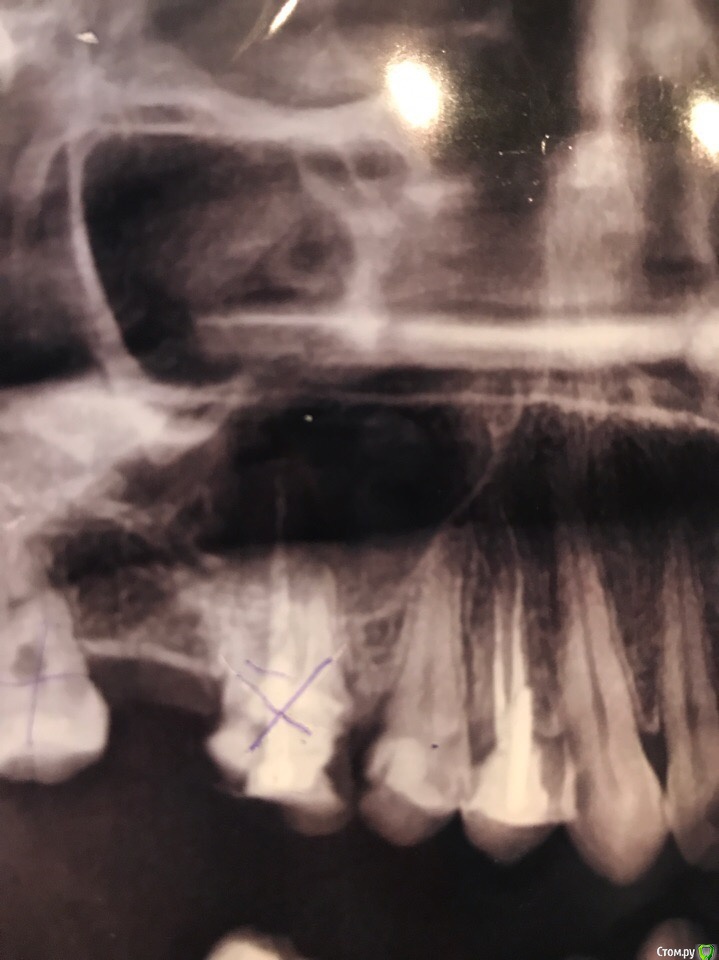

Ульяна 1980 Опубликовано 31 июля, 2018 Поделиться Опубликовано 31 июля, 2018 Добрый день, два месяца назад удалила верхнюю шестерку. Ничего не болело и не болит, ни отека, ни гноя не было. НО лунка не заживает. Спустя месяц обратилась к врачу, лунку почистили, сказали ничего страшного, поверхностное воспаление десны, альвеолит. Опять ничего не болит, но лунка в прежнем состоянии. Пришла через 1,5 недели, смотрели, трогали, нажимали и тыкали, сказали все твердо и все в процессе заживления. Еще через две недели, я обратилась к другому хирургу, сделали снимок. Ему показалось, что там осколок, вскрыли лунку, осколка нет, почистили. Сказали воспаления нет и все внутри хорошо. Прописали мазь солкосерил. Применяла, через неделю у меня лунка все в том же состоянии!!!!!!!! А именно не заживает с одной стороны, по виду как будто там живое мясо. Пришла на осмотр, сказали все ок, а не заживает из за того,что именно там мне чистили и там сгусток. Просьба посмотреть и оценить мой снимок, он сделан вторым хирургом перед чисткой, якобы с осколком. Что не так? Не заживает область десны около пятерки. Также прилагаю снимок до удаления (картинка 3), сделанный год назад. Заранее спасибо. Ссылка на комментарий

Ульяна 1980 Опубликовано 31 июля, 2018 Автор Поделиться Опубликовано 31 июля, 2018 По снимку всё ок. Покажите фото.спасибо! какое фото? области лунки? меня смущает по снимку затемненная область в районе пятерки. И я сейчас понимаю она не связана с удалением, но именно в этом месте не заживает десна. Ссылка на комментарий

kramer Опубликовано 31 июля, 2018 Поделиться Опубликовано 31 июля, 2018 Да все у вас нормально, дайте спокойно зажить десне после удаления и всех кюретажей. Темная область на снимке - гайморова пазуха. 1 Ссылка на комментарий